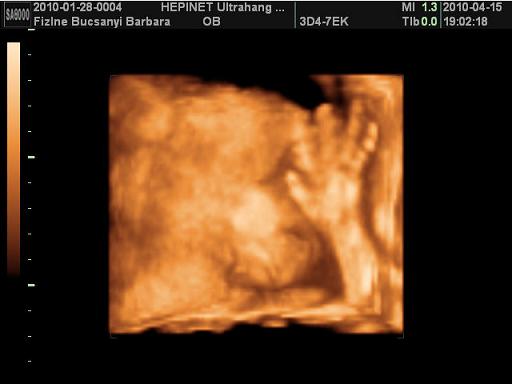

Edi, Bibar: gratu a jó UH-os hírekhez, Kamilláról várjuk ám a képeket, Boti pedig édes kis ManóPofi!